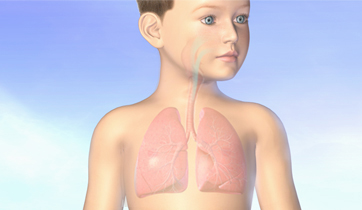

Asthma and its Triggers

Singulair, Merck

Rapp Collins Worldwide

New version in 2012 for UCSF

Patient education animation explaining Asthma and its triggers. The resulting constriction of the airways and the build up of mucus is explained, followed by tactics to maintain airflow and avoid attacks.